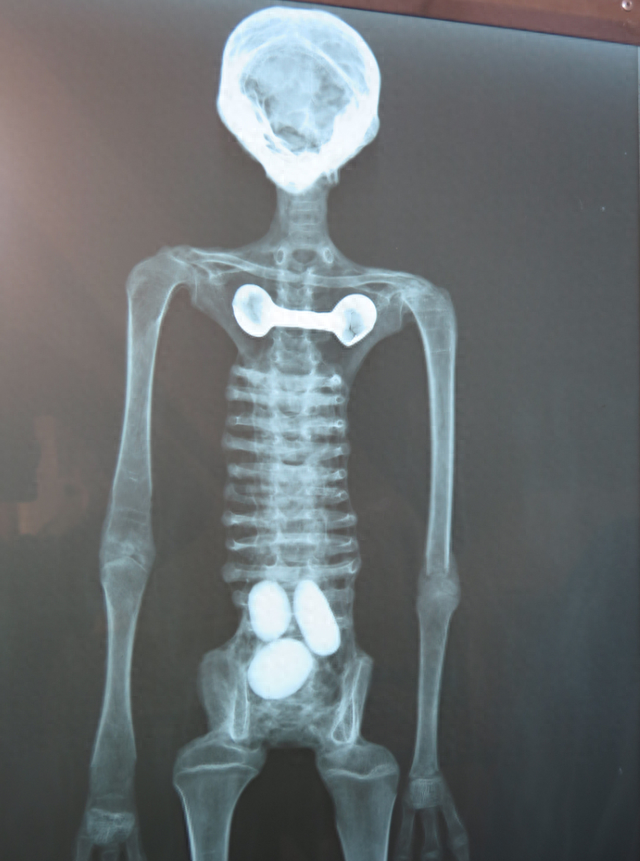

按照莫桑的说法,这些“外星人木乃伊”存在完整的内部构造,但经过X光照射分析,这些所谓的外星人全都是粗制滥造的假货。事实上,所谓的木乃伊确实存在“骨骼结构”,但明显不是自然生长的,而是用人和动物的骨骼拼装而成的。脊柱、肋骨和肢体全部都是用折断的鸟类骨骼拼在一起的,而且没有任何关节相互连接。其中一个代号“E.V.”的木乃伊头骨取自某种小型动物,另一些外星人的头骨则取自猴子和美洲驼。

对这些外星人手腕的扫描后,结果就更离谱了。这些外星人的手部完全是用人类和动物骨骼胡乱拼接的,里面甚至混杂了大量无意义的碎骨,有些指骨甚至是完全颠倒的。显然,通过对人类和动物骨骼的打磨和重新拼接,有人制造了这些完全虚假的“外星人木乃伊”。

而且,这些所谓外星人的体内没有发现任何的内脏痕迹,外星人似乎既不会吃东西,也不会排泄,但在其中一个样本体内居然有三颗蛋!而且,所有的外星人木乃伊都有和人类高度相似的身体构造,基本就是科幻电影里“E.T.”的翻版。在军武菌看来,这种造假方式实在是太缺乏想象力了。